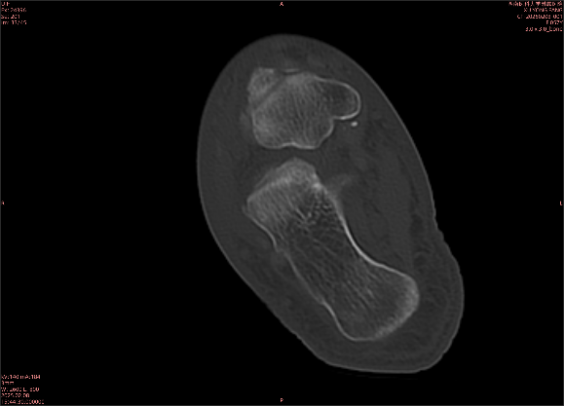

舉例圖像

圖2

專業(yè)解釋看不懂沒關(guān)系,大家看圖1和圖2就可以了,這是同一個患者跟骨的磁共振和CT圖像,圖1的紅色箭頭指示的黑線就是磁共振圖像顯示的骨折線,一目了然。而對比圖2的CT圖像上并未顯示異常。

這下大家明白了吧,如果懷疑隱匿性骨折優(yōu)先選擇磁共振檢查